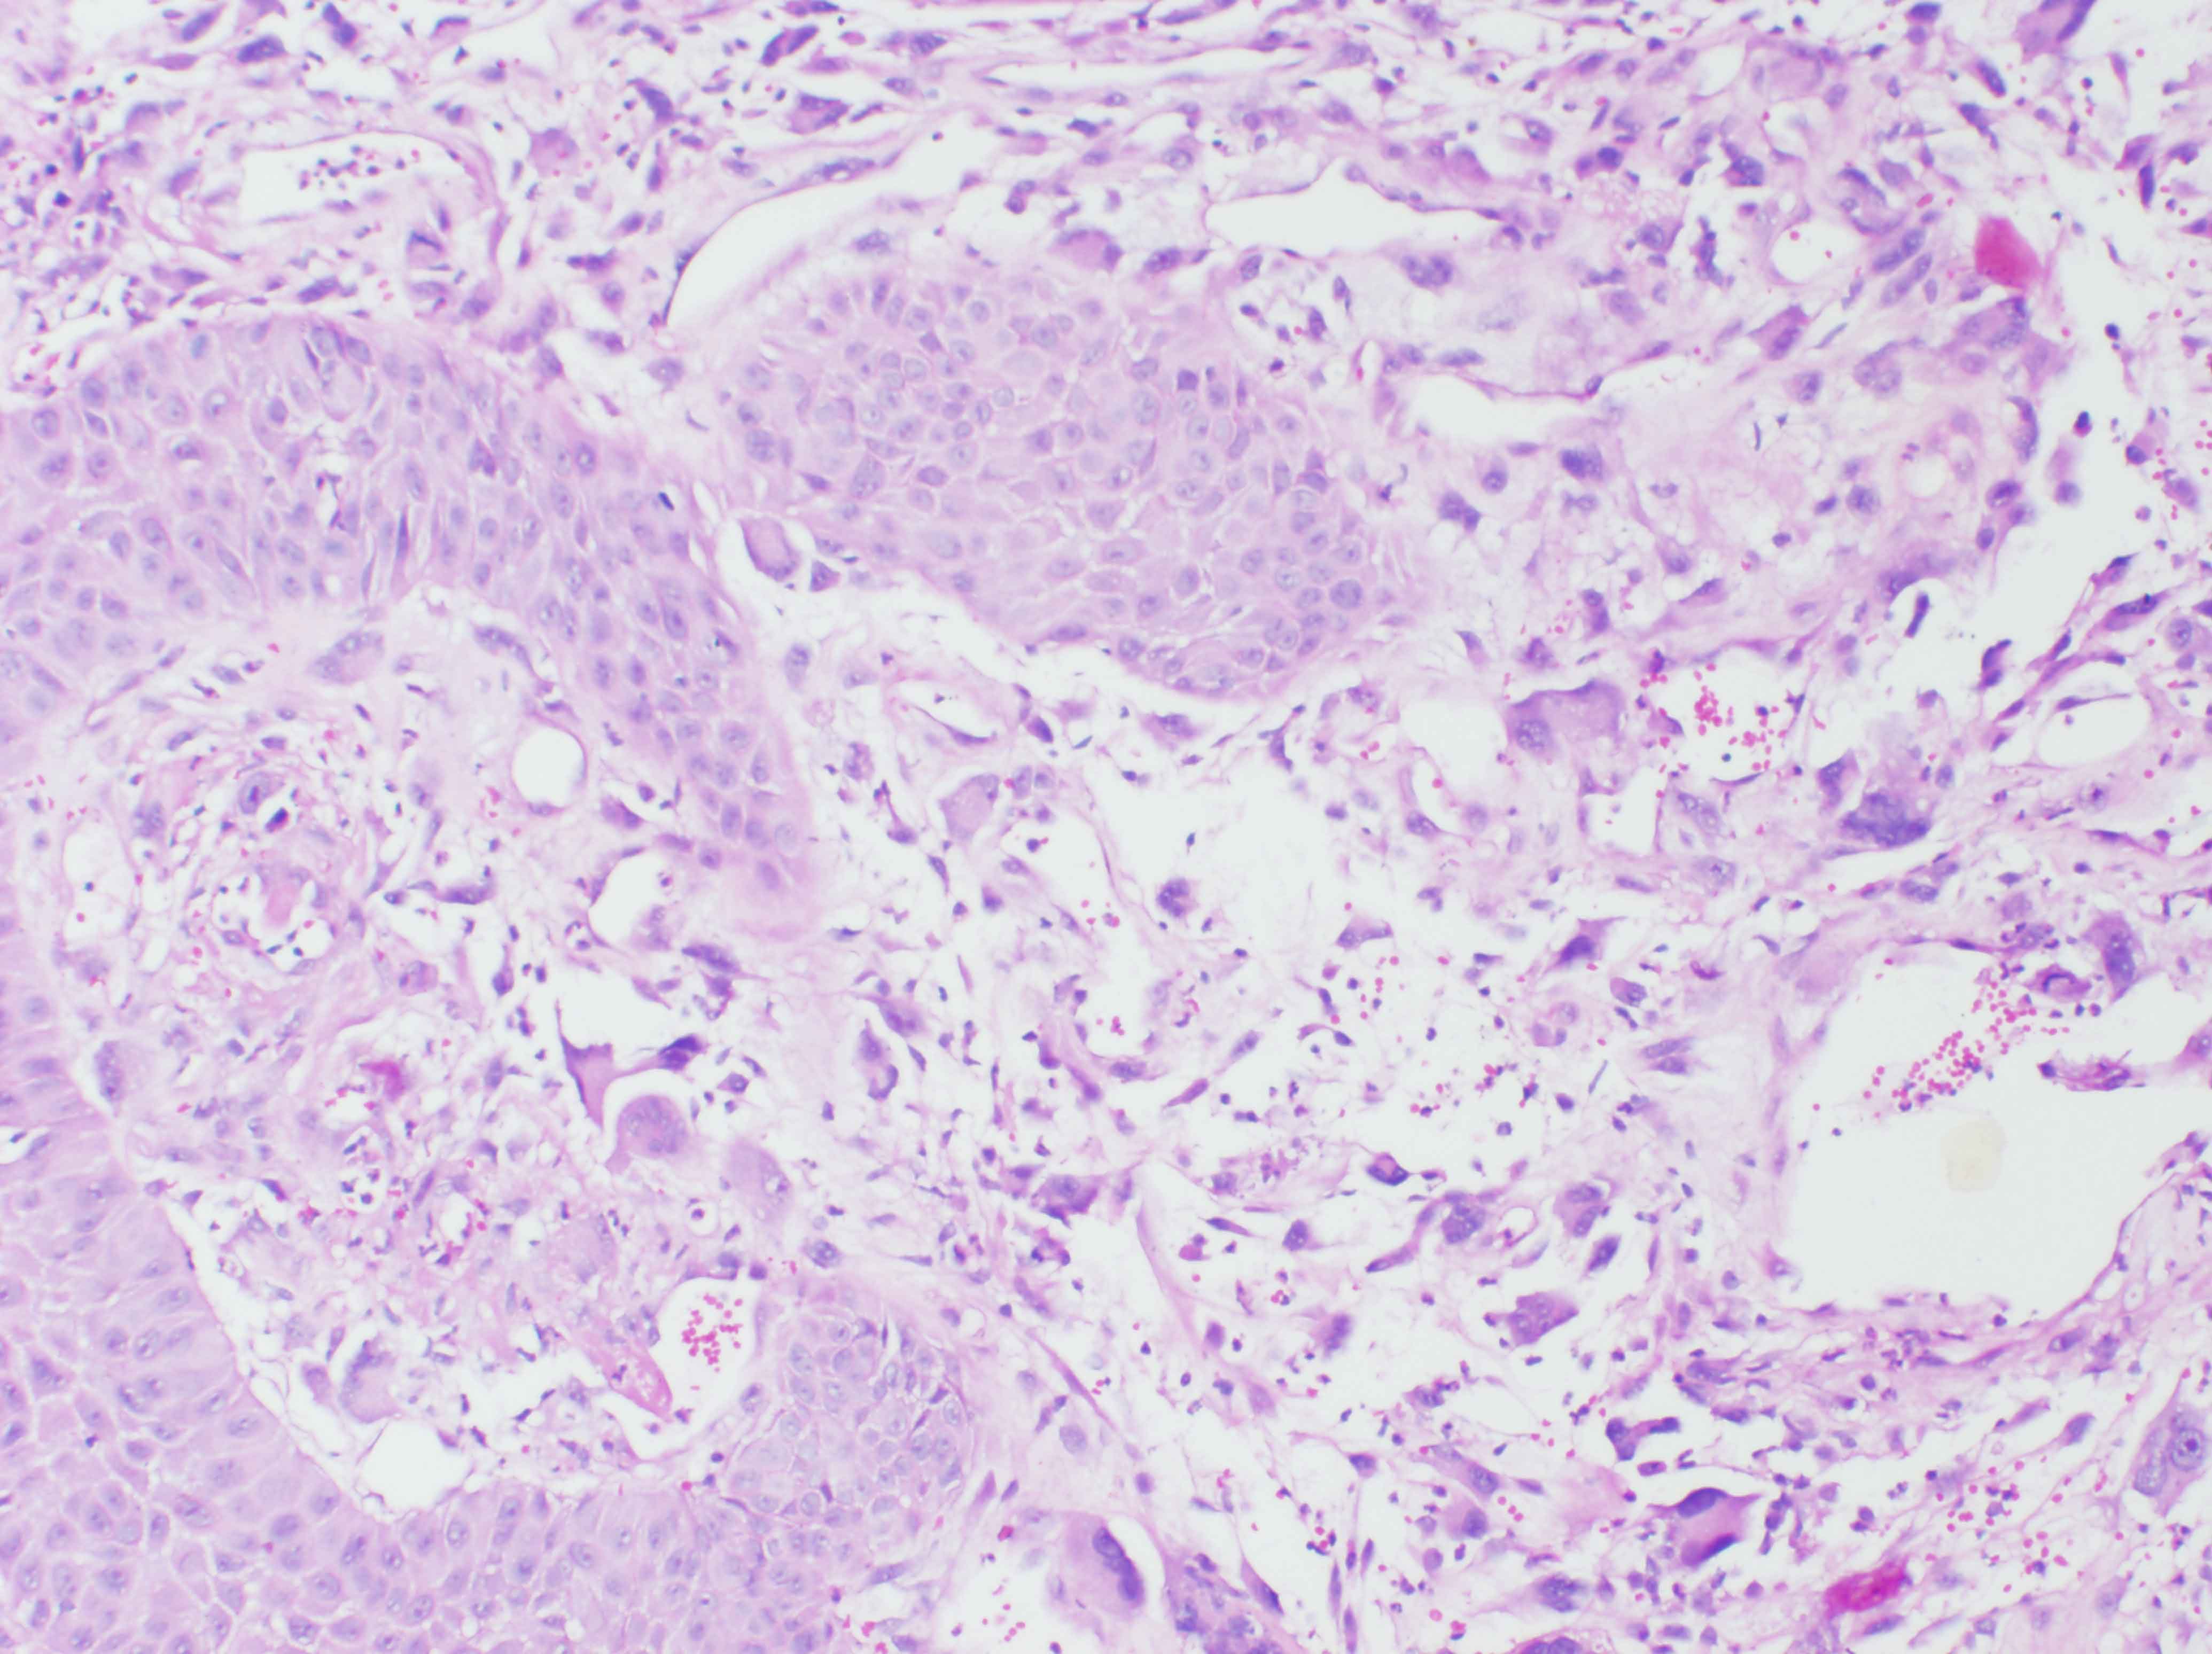

A 67 year male patient reported to Head and Neck Surgery OPD on February 2013 with history of a swelling on the left side of the oral cavity for the past one year. The swelling was insidious in onset, progressively increasing. He had no pain or no difficulty in opening the mouth. He had no history of neck swellings, voice change and respiratory difficulty. He had well differentiated squamous cell carcinoma of the tongue, T2N0M0 for which he underwent wide excision of left lateral tongue with primary closure followed by post-operative radiation of 50 Gy in 15 fractions at November 1994 in our institute. He was on regular followup and detected this swelling presently. He was disease free for a period of 18 years. Patient had no other significant medical illness or other relevant family history. On examination his general condition was fair, moderately built and nourished. Local examination revealed a large 4 x 4cm exophytic, reddish irregular polypoidal mass in the left retromolartrigone (RMT) region with areas of ulceration [Table/Fig-1]. On palpation, mass was firm, non-tender,pedunculated in the left retromolartrigone region. There was no other significant lesion in the oral cavity; initial operated site was normal with no significant induration. No regional lymphadenopathy was noted. Computed tomography (CT) [Table/Fig-2] scan of the lesion showed a large pedunculated lesion of size 2.7x 2x 2.5 cm lesion in the oropharynx originating probably from the left palatoglossal fold, protruding into the left tonsillar fossa. Soft and hard palate was not involved. The lesion is abutting the tip of the medial pterygoid muscle. Punch biopsy from the lesion showed tissue lined by hyperplastic squamous epithelium with sub-epithelium demonstrating infiltrating neoplasm composed of pleomorphic cells [Table/Fig-3] with moderate to abundant cytoplasm, round, irregular pleomorphic nuclei with nucleoli. Multinucleate tumor cells present. Cytokeratin [Table/Fig-4], EMA, HMB45 were negative, whereas Vimentin (mesenchymal tissue marker) [Table/Fig-5] and S-100 protein(nerve fiber) were strongly positive. With a history of pre-existing squamous cell carcinoma and radiation therapy and strongly positive vimentin, diagnosis of sarcoma is made. Treatment option of radical surgery with reconstruction was explained to the patient. As the patient wanted to be on follow up, he is being followed up regularly.

Biopsy showing highly pleomorphic cells beneath the squamous epithelium (H&E × 200)